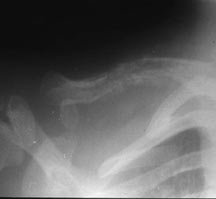

- Any bone but 90% have skull involvement

- Radiographically variable appearance: may appear benign (geographic) or malignant (permeative or moth eaten)

- Skull